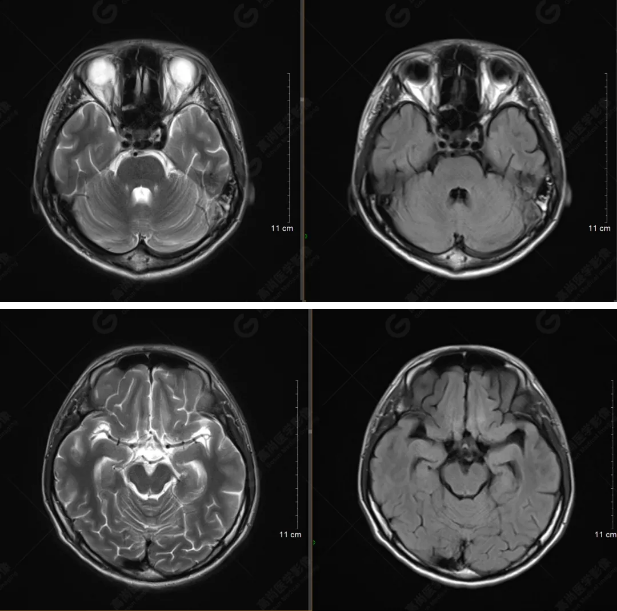

以下是平掃T2WI及FLAIR序列:

雙側(cè)大腦半球?qū)ΨQ,灰白質(zhì)對比正常,顱內(nèi)未見異常信號影。腦室系統(tǒng)未見擴(kuò)大,中線結(jié)構(gòu)居中。腦溝、裂未見增寬。幕下小腦、腦干未見異常。矢狀位示垂體形態(tài)、大小級信號未見異常。所示左側(cè)乳突內(nèi)見多發(fā)短T1長T2信號影。

顱腦MRI平掃未見明顯異常,左側(cè)乳突內(nèi)積血,建議補(bǔ)充SWI檢查。(左側(cè)為薄層原始圖像,右側(cè)為后處理5mm圖像)